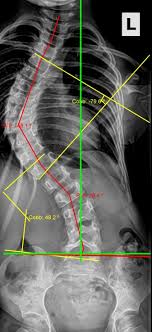

يناقش الطبيب خيار الجراحة عندما تتجاوز زاوية الانحناء 45 إلى 50 درجة، أو عندما يستمر الاعوجاج في التفاقم رغم العلاج التحفظي. تهدف الجراحة إلى تصحيح الانحناء قدر الإمكان ومنع حدوث مضاعفات مستقبلية، ويُتخذ القرار بعد تقييم شامل للحالة.